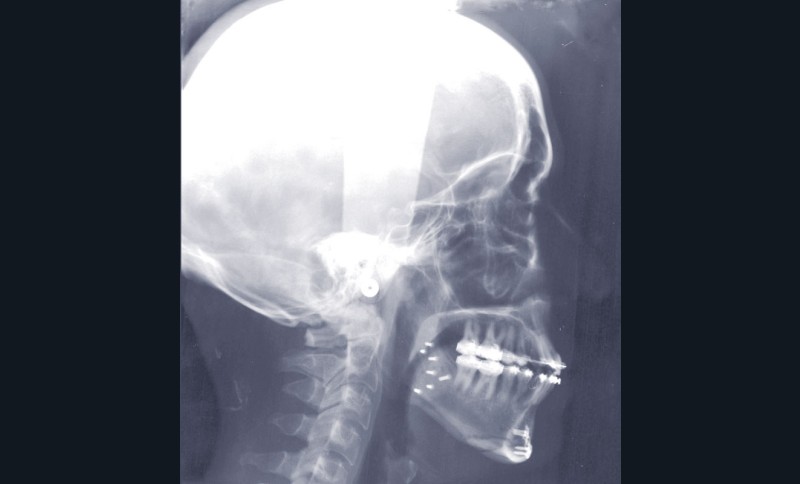

Étapes de traitement

(fig. 2, 3, 4, 5 et 6)

– chirurgie d’avancée mandibulaire et génioplastie soustractive verticale